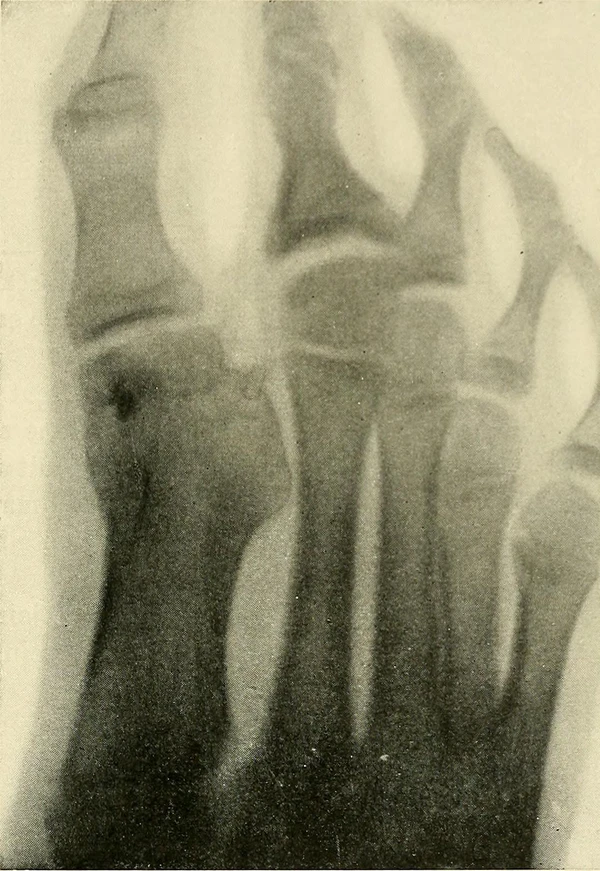

Для диагностики применяют рентгенографию или компьютерную томографию области перелома[2].